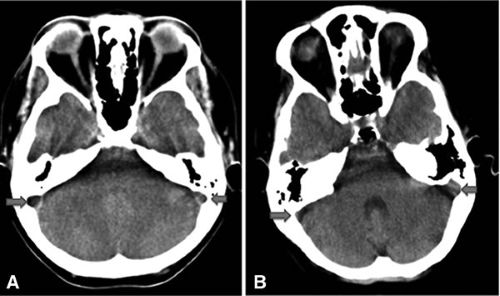

Тромбоз сигмовидного синуса выявляется при:

- МРТ ангиографии сосудов головного мозга

- СКТ сосудов головного мозга с контрастированием